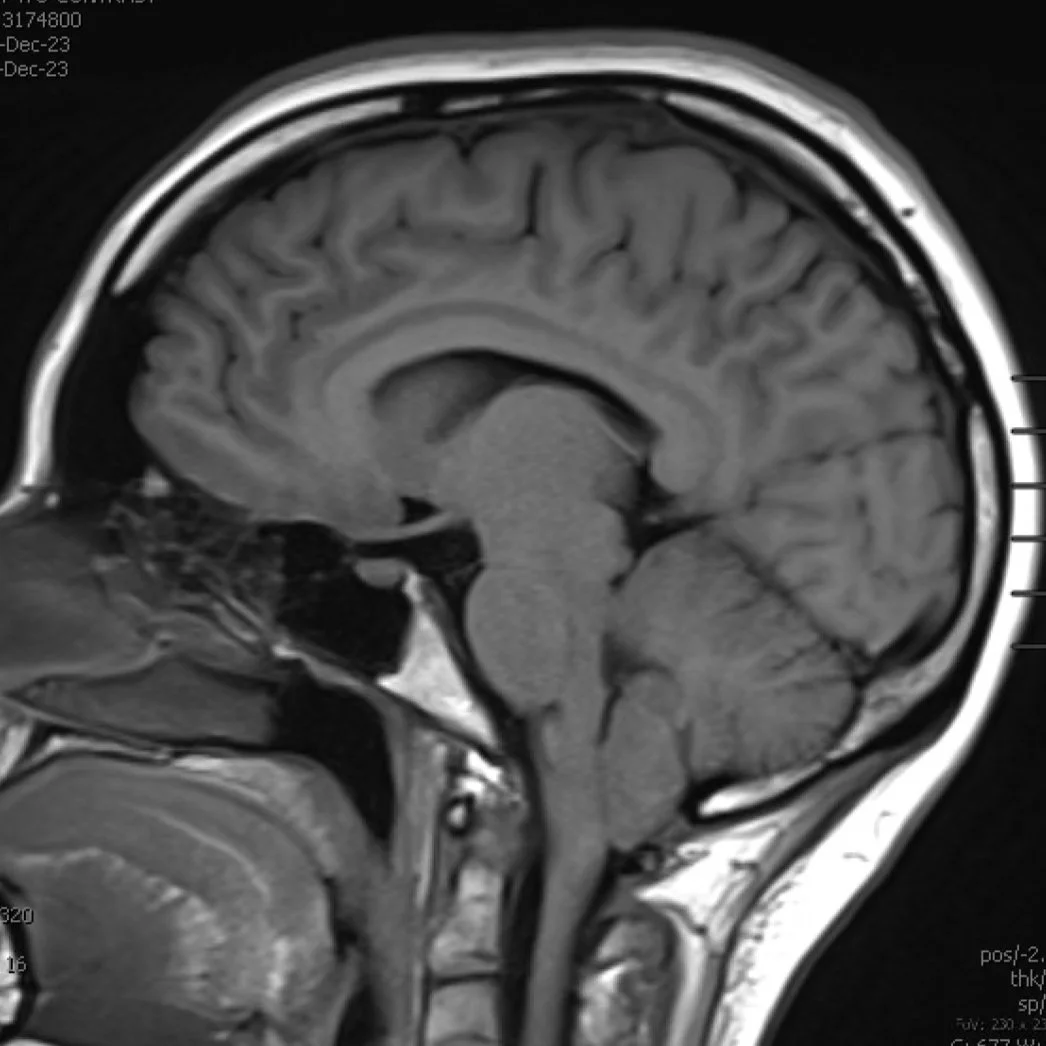

Brain

Learn More